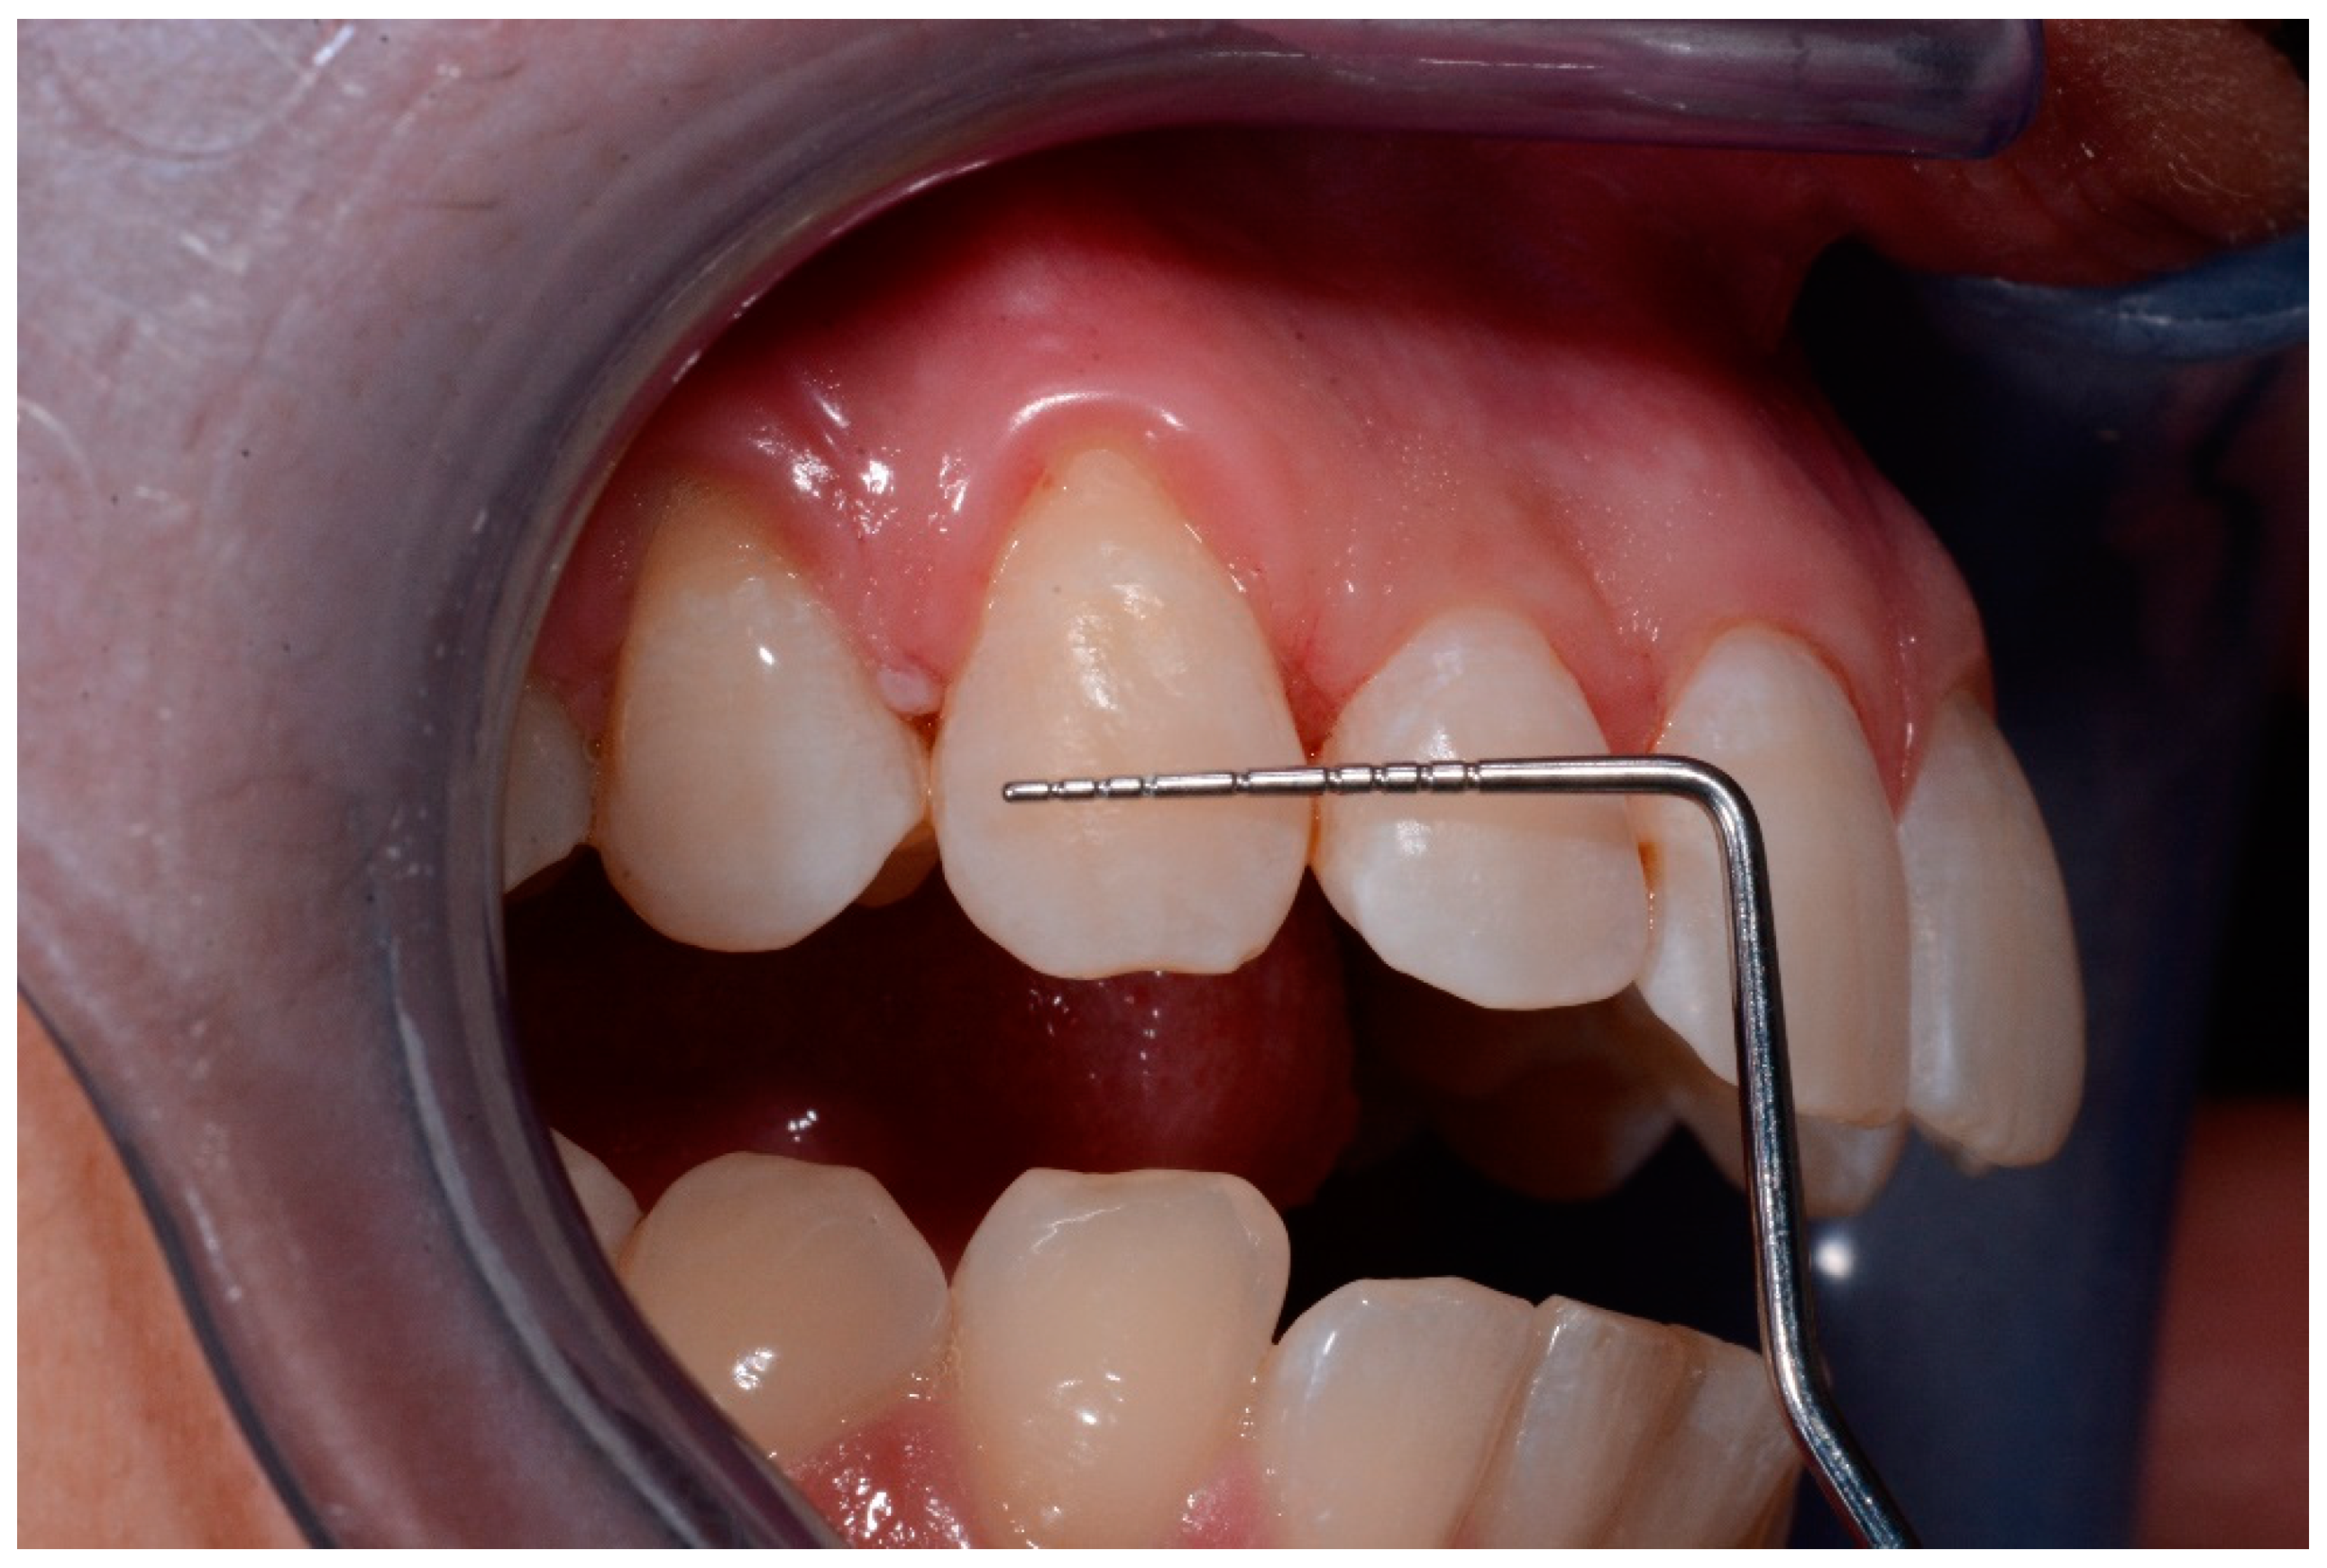

- The main dimension of lesions (mm)